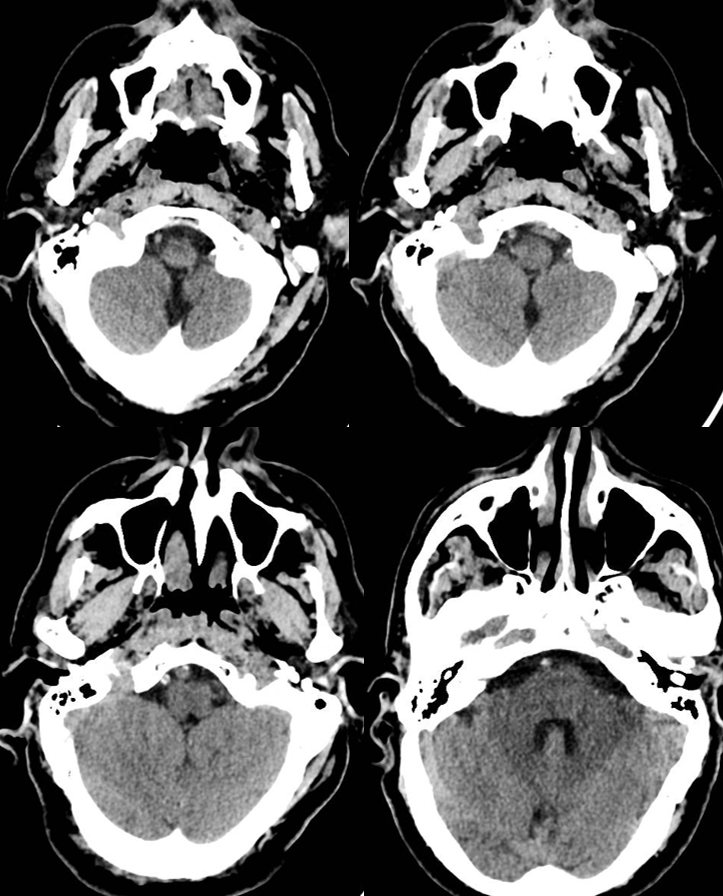

VB junction occlusion

Leptomeningeal anastomoses are just as present and as variable as in the supratentorial compartment